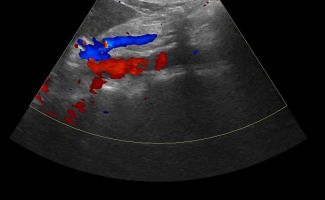

- Αιμοδυναμικές Διαταραχές: Mε τη χρήση του Έγχρωμου και του Παλμικού Doppler μπορούν να μελετηθούν οι ταχύτητες της αιματικής ροής και να ανιχνευθούν πιθανές αιμοδυναμικές διαταραχές.

- Αγγειακή Στένωση: Η αξιολόγηση της αιματικής ροής μπορεί να οδηγήσει στη διάγνωση στένωσης των αγγείων και να υπολογιστεί ο βαθμός της στένωσης.